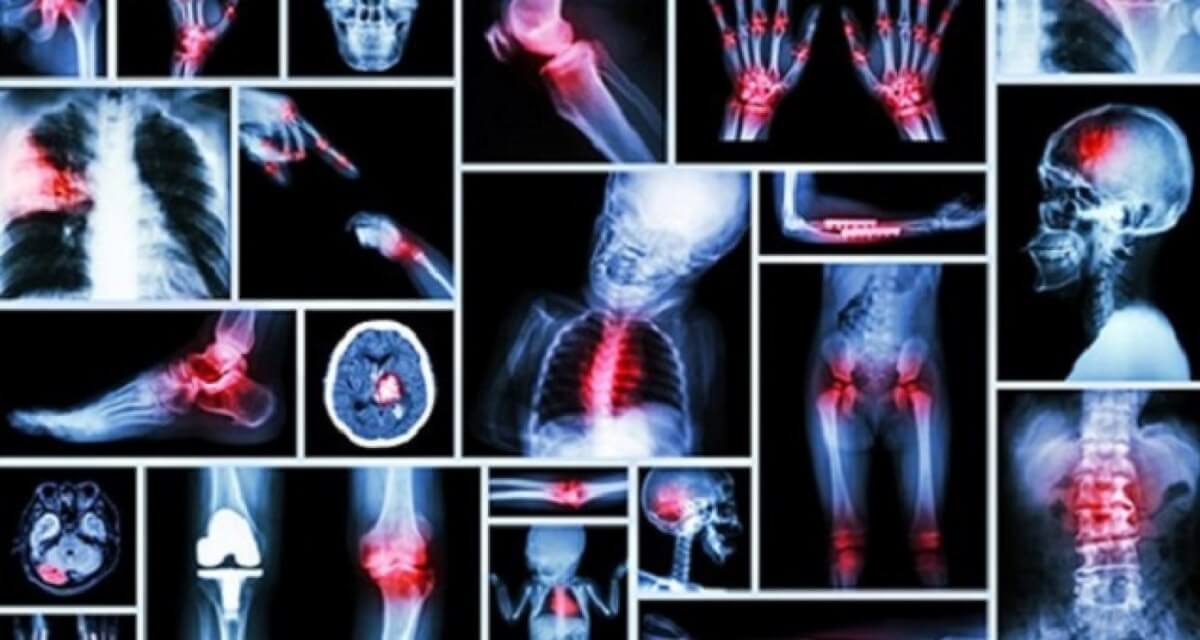

10 dores que estão ligadas diretamente com os sentimentos e as emoções

Um grande exemplo dessa integração é a conclusão da doutora em psicologia Susanne Babbel. Depois de um minucioso estudo, a dra. Babbel concluiu que boa parte das dores crônicas que sentimos não tem nada a ver com doenças graves ou lesões anteriores.

Ela acredita que adquirimos a maioria das dores com emoções negativas  – como o estresse – que acabam afetando alguns órgãos.

O estudo da psicóloga resultou num “mapa” que mostra como as emoções interferem na saúde. Este post vai mostrar a você esse “mapa” e como você pode tratar e neutralizar os efeitos negativos das emoções.